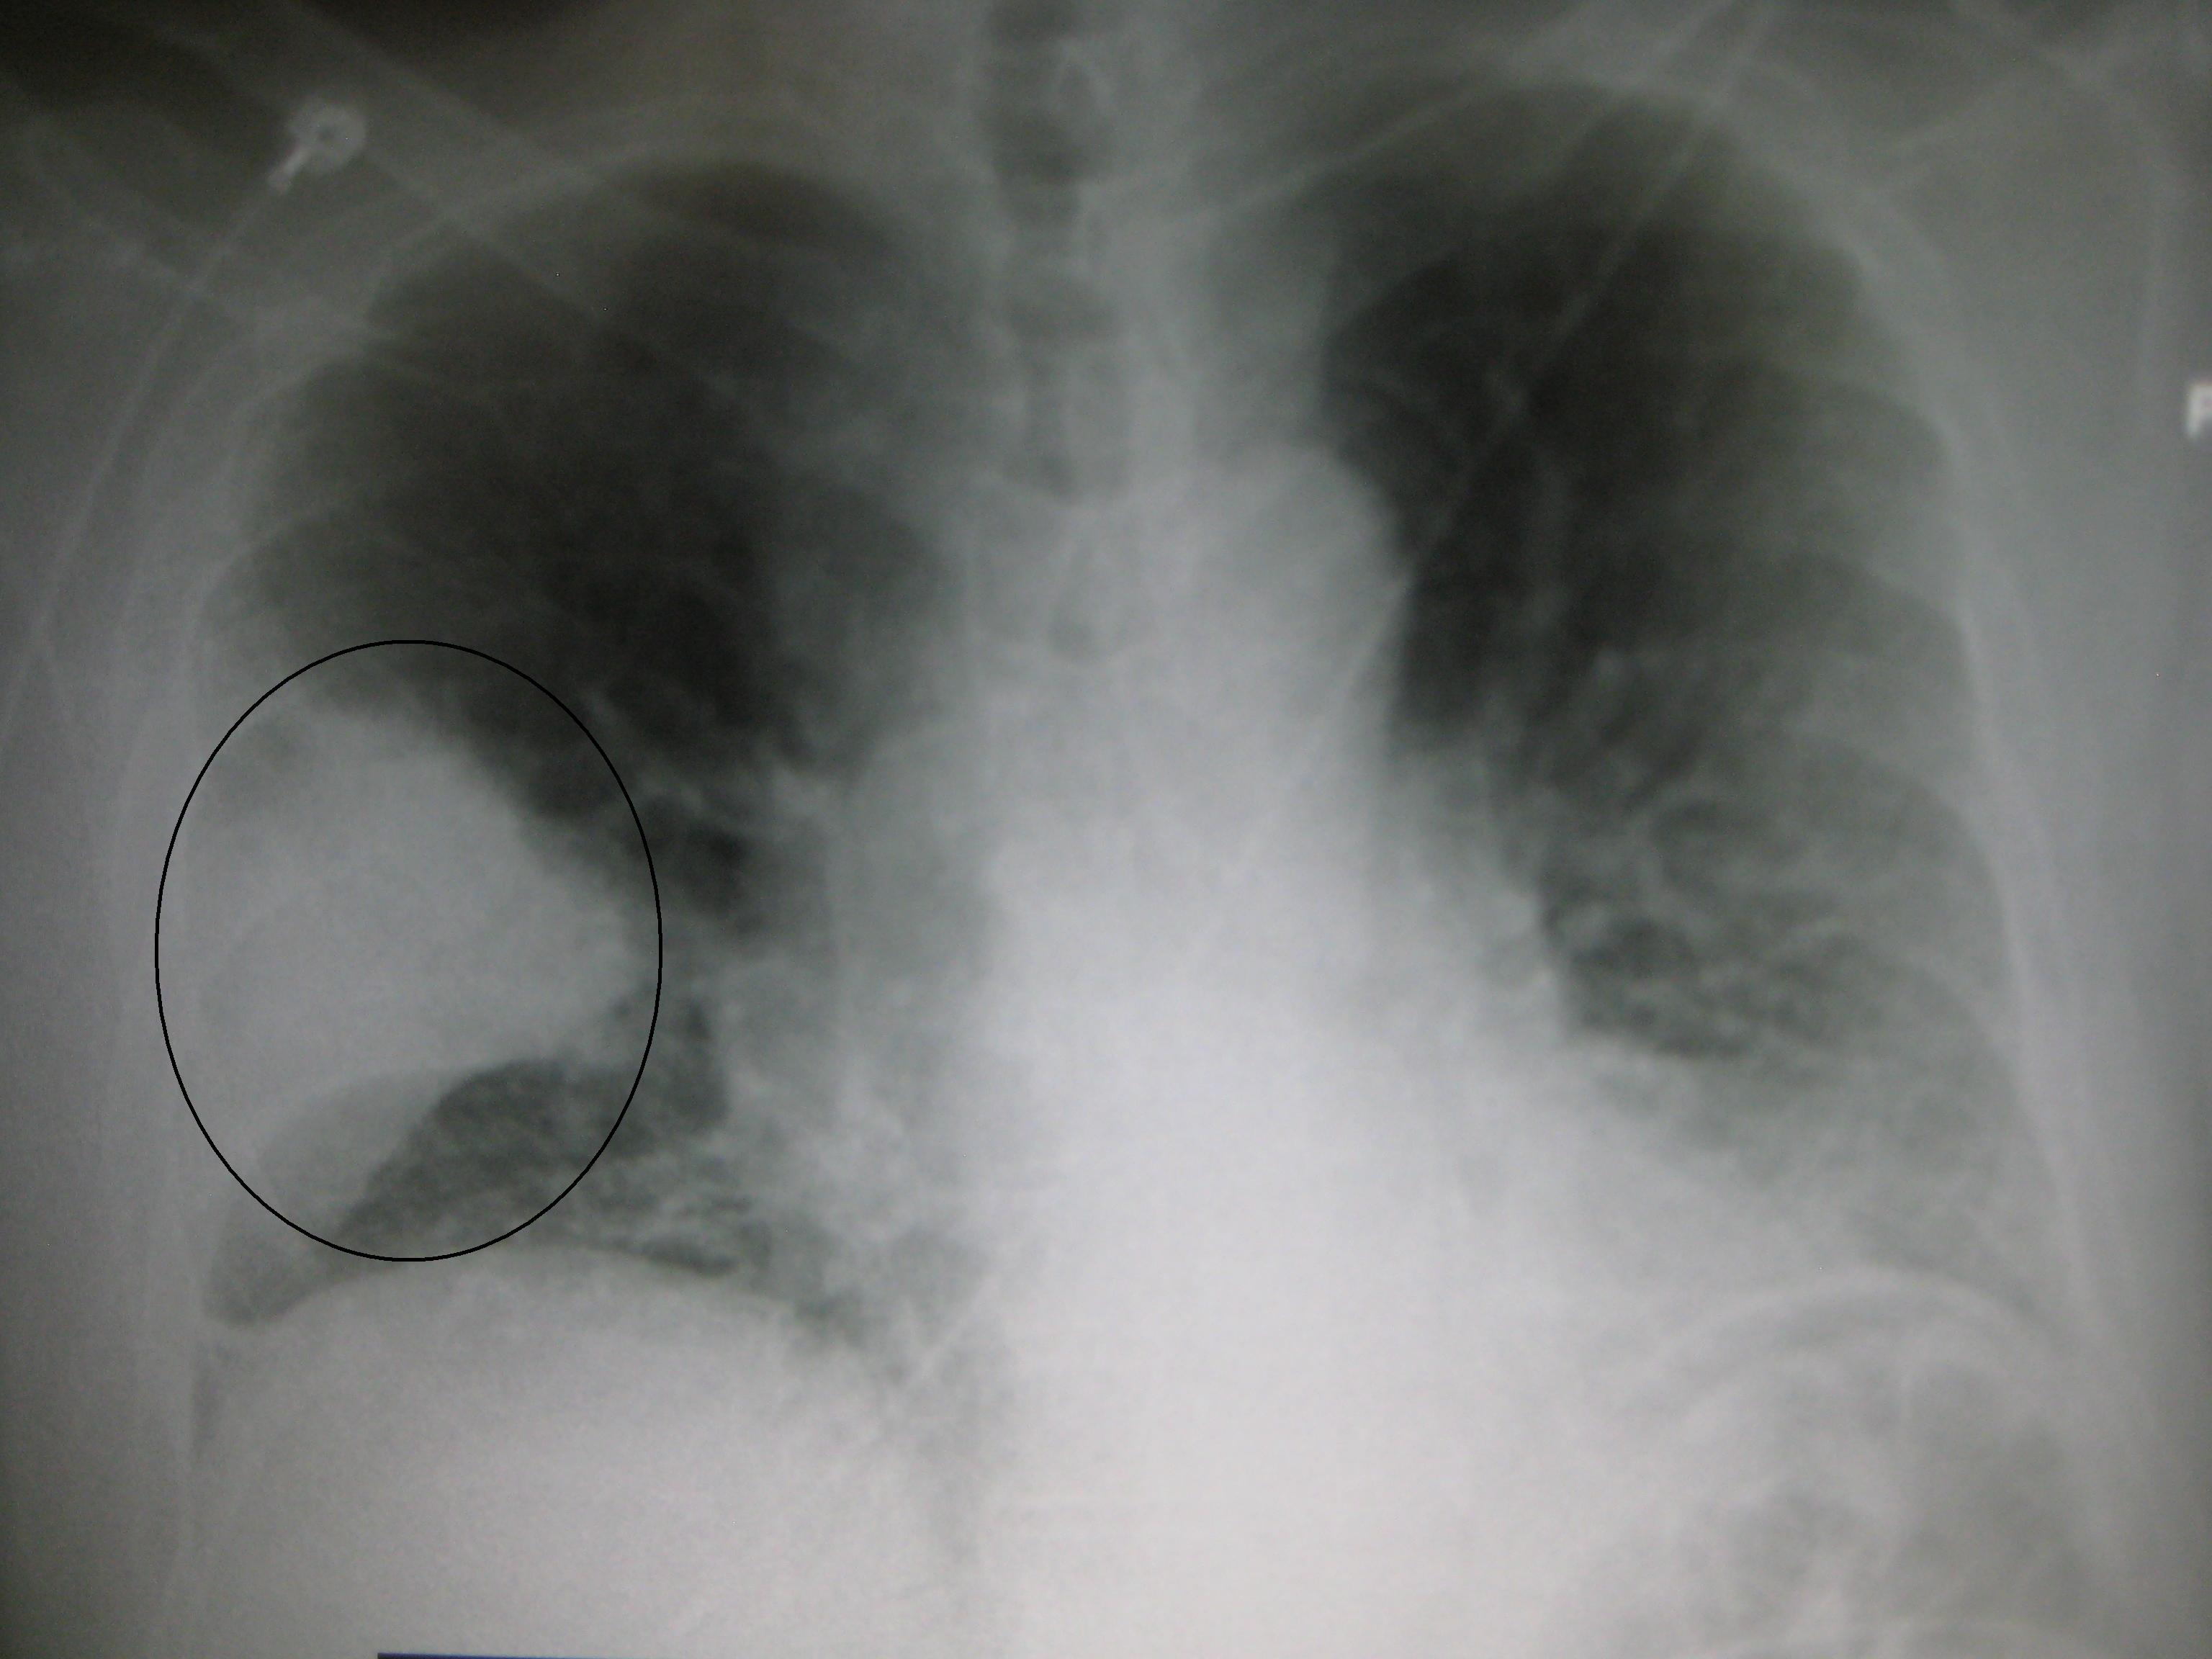

Зверніть увагу, що симптоми і те, як хвороба виглядає на рентгенівських знімках, сильно нагадує туберкульоз або центральний рак легені.

Діагностика викликає труднощі через атипового розташування запального процесу. Звичайне рентгенологічне дослідження визначає розширення середостіння, але не дає достовірної інформації про наявність вогнища запалення, тому з’являється необхідність проведення диференційної діагностики з туберкульозом і центральним раком легенів.

Одним з провідних діагностичних досліджень є рентгенографія органів грудної клітки. На знімку можна побачити розширення легеневого кореня, вогнища в зоні проекції коренів легень.

Комп’ютерна томографія дозволяє уточнити дані рентгенографії і провести диференціальний діагноз отриманого рентгенівського зображення з такими захворюваннями, як рак легень, туберкульоз, які супроводжуються подібною клінічною та рентгенологічною симптоматикою.

Справа в тому, що у випадку саме цього захворювання рентгенівські знімки можуть бути неправильно інтерпретовані.

Вогнище хвороби дає тінь і розширення кореня у легені. У цьому випадку можливі помилкові постановки діагнозу.

Щоб поставити точний діагноз прикореневій форми пневмонії, проводяться рентгенологічні обстеження. Ознаки її на знімках виражаються маленькими, світлими, округлими ділянками на легеневої тканини. Пройшовши рентген, його слід показати лікарю та отримати консультацію.